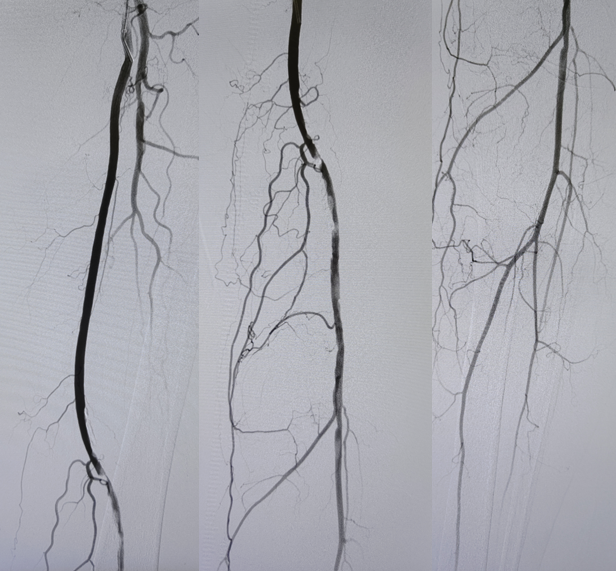

冲击波球囊在严重钙化病变中的应用

对于严重钙化病变,传统球囊扩张效果不佳,夹层发生率高。冲击波球囊(IVL)技术为处理钙化病变提供了新选择。Disrupt PAD III研究显示,与单纯POBA+DCB相比,IVL+DCB方案的手术成功率更高(65.8% vs. 50.4%),限流性夹层发生率更低(1.4% vs. 6.8%),补救支架植入率显著降低(4.6% vs. 18.3%),且2年一期通畅率更优(70.3% vs. 51.3%)。IVUS在此类病变中能精准评估钙化范围和程度,指导IVL球囊的尺寸选择和治疗位点。

图:严重钙化病变

图:钙化病变

图:5.0震波球囊

图:DCB处理